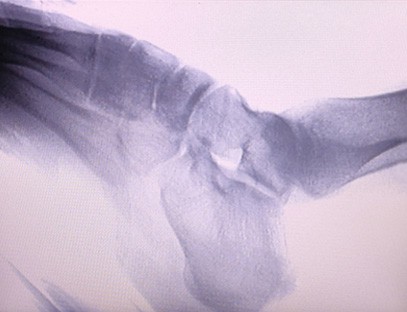

Prijenosni rendgenski aparatje vrlo siguran prijenosni instrument s niskom dozom zračenja koji može dobiti visokokvalitetne slike uz smanjenje izloženosti zračenju. Kompenzira nedostatke velike bolničke opreme i može se pomicati i nositi u bilo koje vrijeme. Posebno prikladno za jedinice i pojedince s nedovoljnim proračunom i malim zahtjevima za slike. Naš rendgenski uređaj nove generacije opremljen je velikim zaslonom visoke razlučivosti od 10 inča, koji ima veći raspon kuta gledanja i može u potpunosti vidjeti kroz cijeli dlan, uključujući prijelome, iščašenja, artritis i tumore kostiju. Može se spojiti na filmski pisač za ispis ortopedskih filmova, a može se koristiti i za industrijsku proizvodnju i testiranje. Nema potrebe za mračnom komorom, izravna perspektiva, promatranje u stvarnom vremenu. Ovaj stroj ima slikovni sustav visoke rezolucije koji može vrlo jasno uhvatiti slike bilo koje koštane strukture. Osigurati najbolju opremu i rješenja za testiranje rendgenskih zraka za proizvođače medicinskih, kućnih ljubimaca, industrijskih i elektroničkih proizvoda, odjele za inspekciju i održavanje te istraživačke laboratorije.

Specijalizacija:Dizajniran za potrebe ortopedskih klinika, posebno pogodan zaRentgensko snimanjeudova kao što su ruke, zglobovi, laktovi, ramena, koljena, gležnjevi itd.

Jasna slika:Napredna digitalna tehnologija snimanja koristi se za dobivanje visokokvalitetnih rendgenskih slika, pomažući liječnicima da točno dijagnosticiraju stanje.